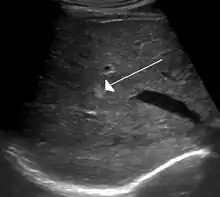

Hemangiomas (do grego haema- (αίμα), "sangue"; angeio (αγγείο), "vaso"; -oma (-ωμα) "tumor") são angiomas, tumores vasculares benignos causados por um crescimento anormal de vasos sanguíneos que geralmente não causam danos, apenas são desagradáveis esteticamente. São mais comuns na pele, especialmente na cabeça e pescoço, mas podem aparecer em vários órgãos, como o fígado, o baço, o pâncreas, na boca ou em bolsas sinoviais.